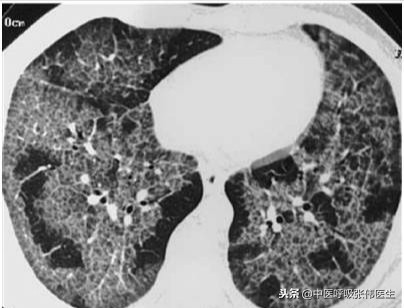

2.胸部CT检查

PAP肺部受累范围和类型,其作用优于胸部X线平片,尤其高分辨CT(HRCT)可呈毛玻璃状和(或)网状及斑片状阴影,可为对称或不对称性,有时可见支气管充气征。病变与周围肺组织间常有明显的界限且边界不规则,形成较特征性的“地图样”改变。病变部位的小叶内间隔和小叶间间隔常有增厚。